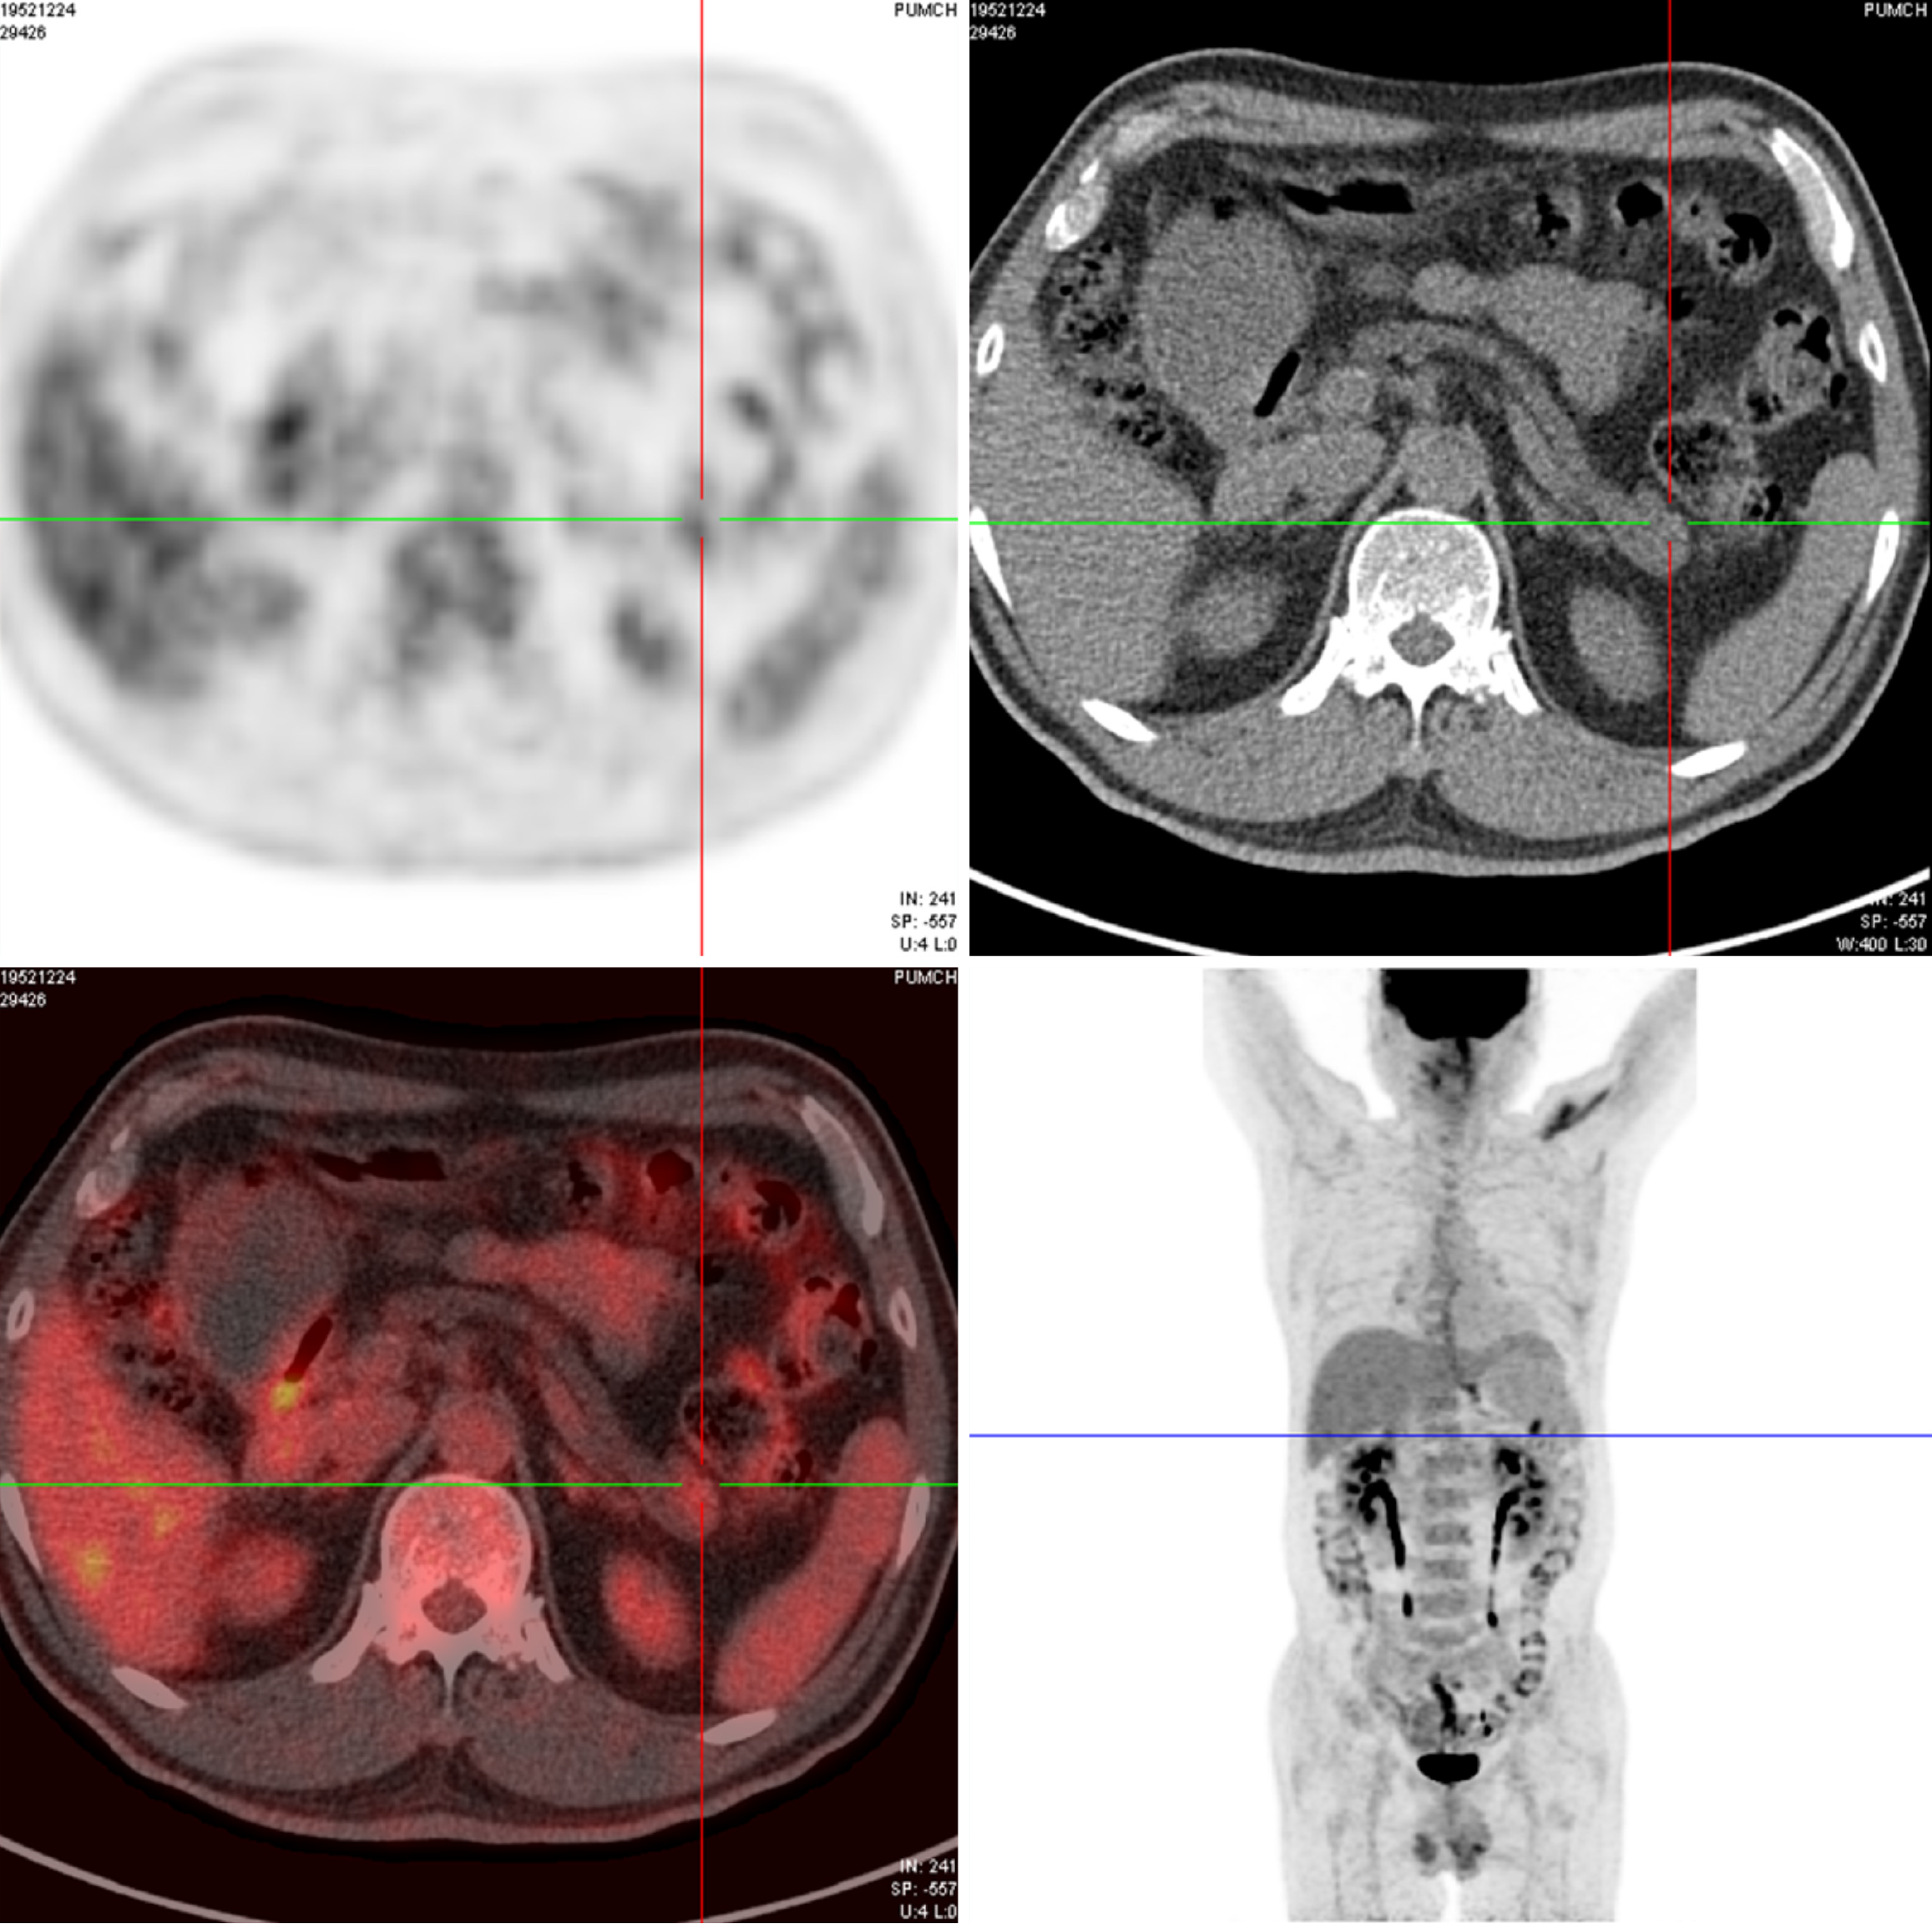

Figure 2 Positron emission tomography-computed tomography of the patient.